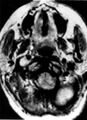

التشخيص

طرق العلاج الرئيسية هي الجراحة والانصمام[12] والعلاج الإشعاعي.[13]